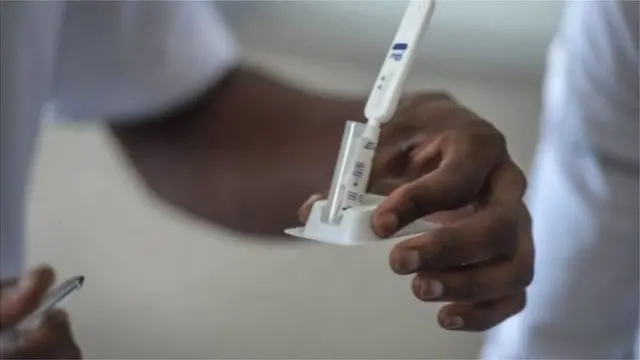

ایچ آئی وی انفیکشن کا پتہ چلا

،تصویر کا ذریعہGetty Images

رخسانہ نے بتایا کہ ’جیسے ہی میں پولیس سٹیشن پہنچی، منوجی نے بھی پولیس سٹیشن میں سرینڈر کر دیا۔ یہاں سے ہی ہمارے لیے پریشانی شروع ہو گئی۔ مجھے خواتین کی پناہ گاہ میں رکھا گیا تھا۔ پولیس نے میرا میڈیکل ٹیسٹ کرایا اور پھر پتا چلا کہ میں ایچ آئی وی سے متاثرہ ہوں۔ میں بُری طرح سے ٹوٹ گئی تھی۔ مجھے ڈر تھا کہ کہیں مانوجی بھی ایچ آئی وی سے متاثر تو نہیں ہیں۔ ان کا بھی ٹیسٹ کرایا گیا تھا۔ ڈاکٹروں نے انھیں بتایا کہ وہ ایچ آئی وی سے متاثر نہیں ہیں۔ پھر مجھے سکون آيا۔‘

مانوجی نے بتایا کہ ’میں نے پولیس کو بتایا کہ میرے پاس اس بات کا ثبوت ہے کہ میں نے ایک بالغ لڑکی کی رضامندی سے شادی کی ہے لیکن کوئی مجھ پر اعتماد نہیں کر رہا تھا۔ کیس عدالت چلا گیا۔ دو ماہ تک جیل میں رہنے کے بعد مجھے گجرات ہائی کورٹ سے ضمانت مل گئی۔ لیکن میرا سارا دھیان میڈیکل ٹیسٹ پر تھا۔‘

گجرات ہائی کورٹ میں مانوجی کا مقدمہ لڑنے والے وکیل اپوروا کپاڈیا نے بی بی سی کو بتایا کہ یہ ایک عجیب و غریب معاملہ تھا۔ مانوجی ایچ آئی وی سے منفی تھے، لیکن طبی افسروں کو خدشہ تھا کہ وہ چھ ماہ کے اندر اس بیماری کی زد میں آ سکتے ہیں۔

اپوروا کپاڈیا نے کہا ’چھ ماہ بعد منوجی کا دوسرا ایچ آئی وی ٹیسٹ احمد آباد سول ہسپتال میں ہوا اور اس کا نتیجہ بھی منفی تھا۔ اس دوران مانوجی کو رخسانہ سے شیلٹر میں ملنے کی اجازت دی گئی تھی۔ رخسانہ کے والد نے عدالت میں جھوٹے ثبوت دیتے ہوئے اسے نابالغ ثابت کرنے کی کوشش کی۔‘

’عدالت کی جانب سے مانوجی سے بھی پوچھا گیا تھا۔ انھیں بتایا گیا تھا کہ رخسانہ کو ایچ آئی وی ہے۔ مستقبل میں یہ آپ کے ساتھ بھی ہو سکتا ہے۔ ایسی صورتحال میں وہ اپنی شادی کے فیصلے پر کیا غور کرنا چاہیں گے؟ مانوجی نے عدالت کو بتایا کہ وہ شادی برقرار رکھنا چاہیں گے۔‘